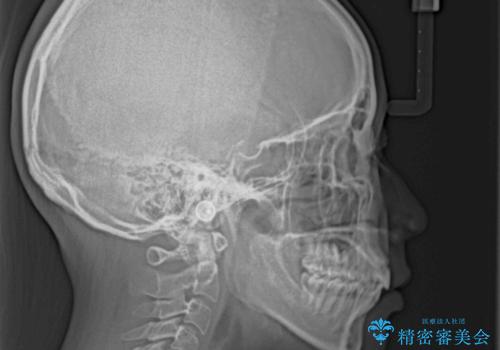

- 前歯の出っ歯と口元の閉じにくさを気にして来院された患者様です。

口元を積極的に引っ込めるために、上下左右の小臼歯4本を抜歯することとしました。

4本の歯を抜歯したことで、飛び出していた口元が引っ込み、横顔の印象が大きく改善されました。